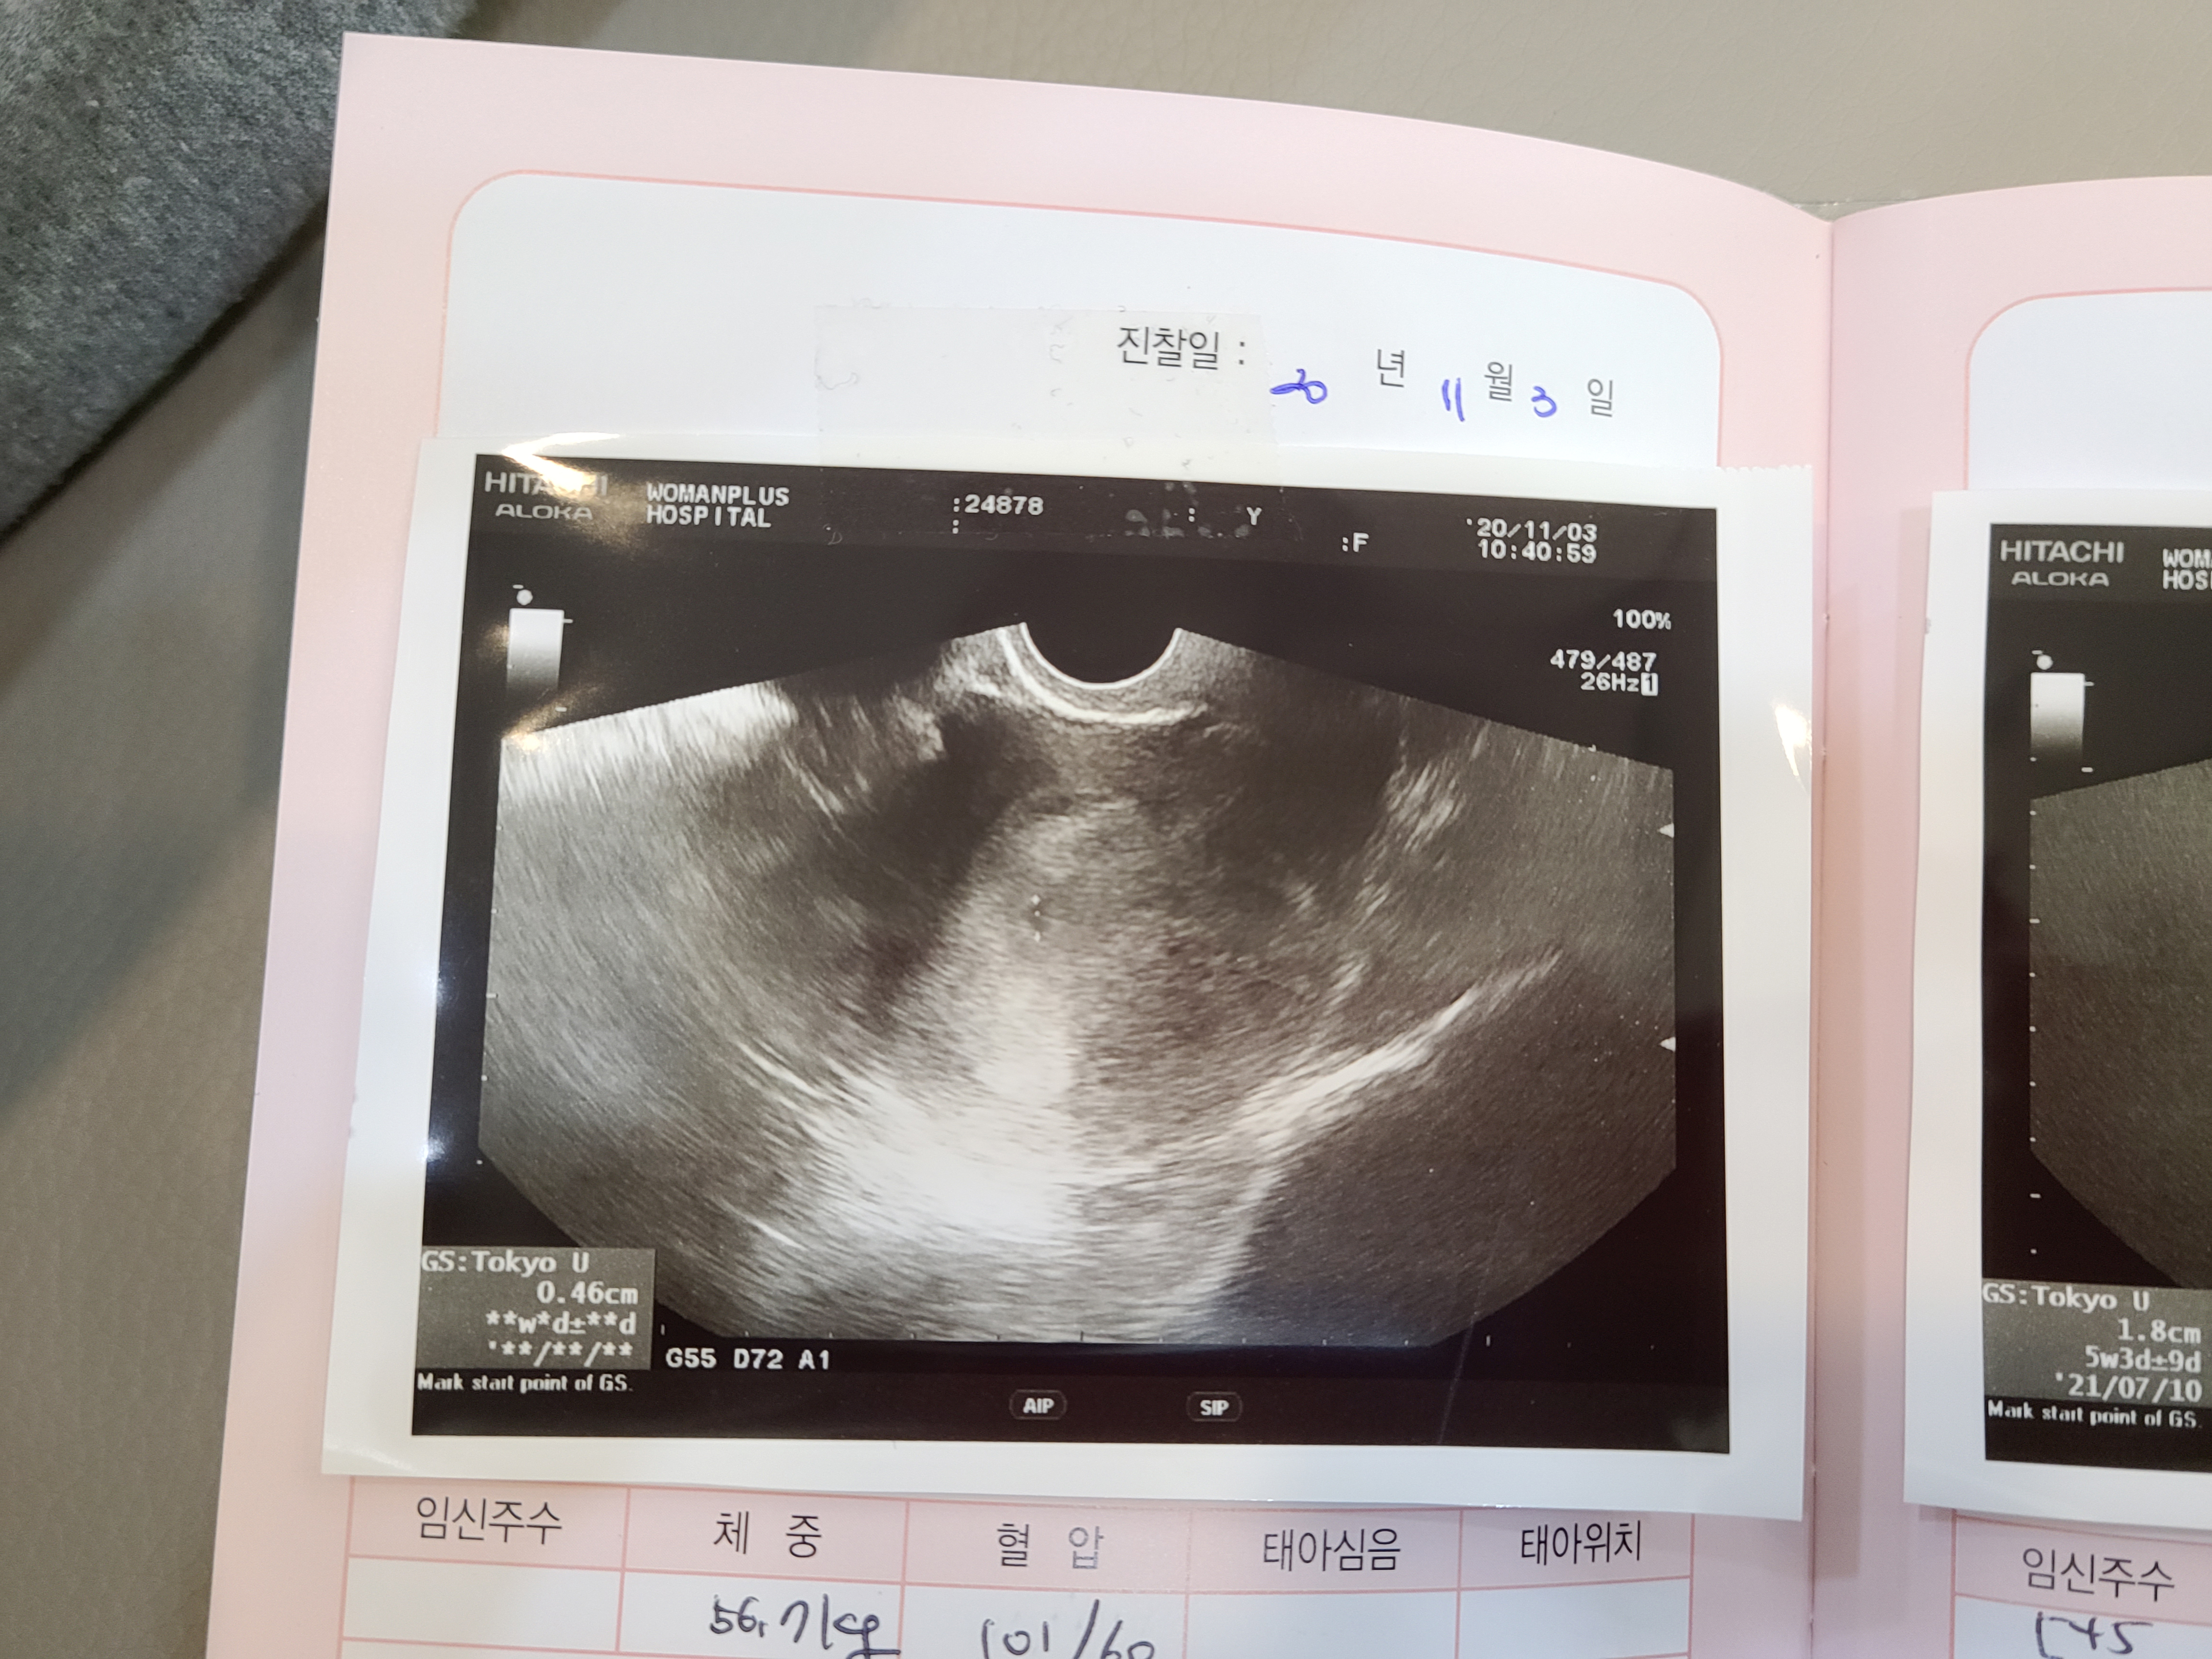

처음 너는 세포 분열 중이였어.

두번째, 이제 니가 처음 보이기 시작했어